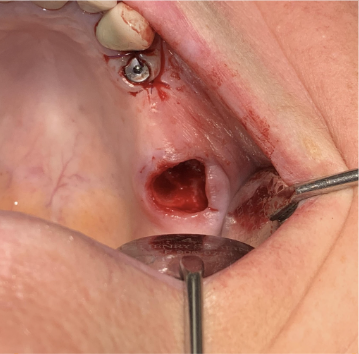

Patient se présente avec fracture de la 27 pilier de bridge.

Objectif : préservation osseuse alvéolaire résiduelle sur un site présentant une faible quantité d’os et le sinus en proximité immédiate.